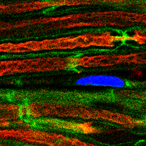

Proximity to nearby muscle cells may make prostate cancer cells more likely to invade nearby tissues and spread to other organs, according to an early study by researchers at the National Institutes of Health. The presence of muscle cells appears to make cancer cells more likely to fuse two or more cancer cells into a single cell, thereby increasing their invasiveness and ability to spread.